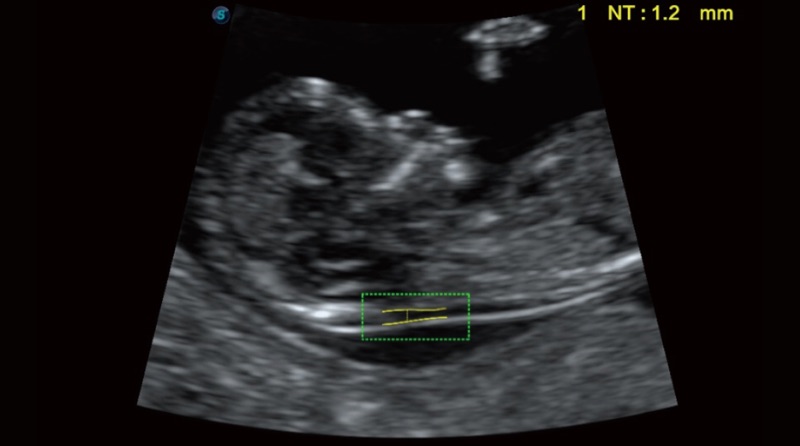

Automatinis NT

„Auto NT“ užtikrina pusiau automatinius, standartizuotus nuchalinio peršviečiamumo storio matavimus 2D vaizde ir sumažina operatoriaus priklausomybę nuo rezultatų.